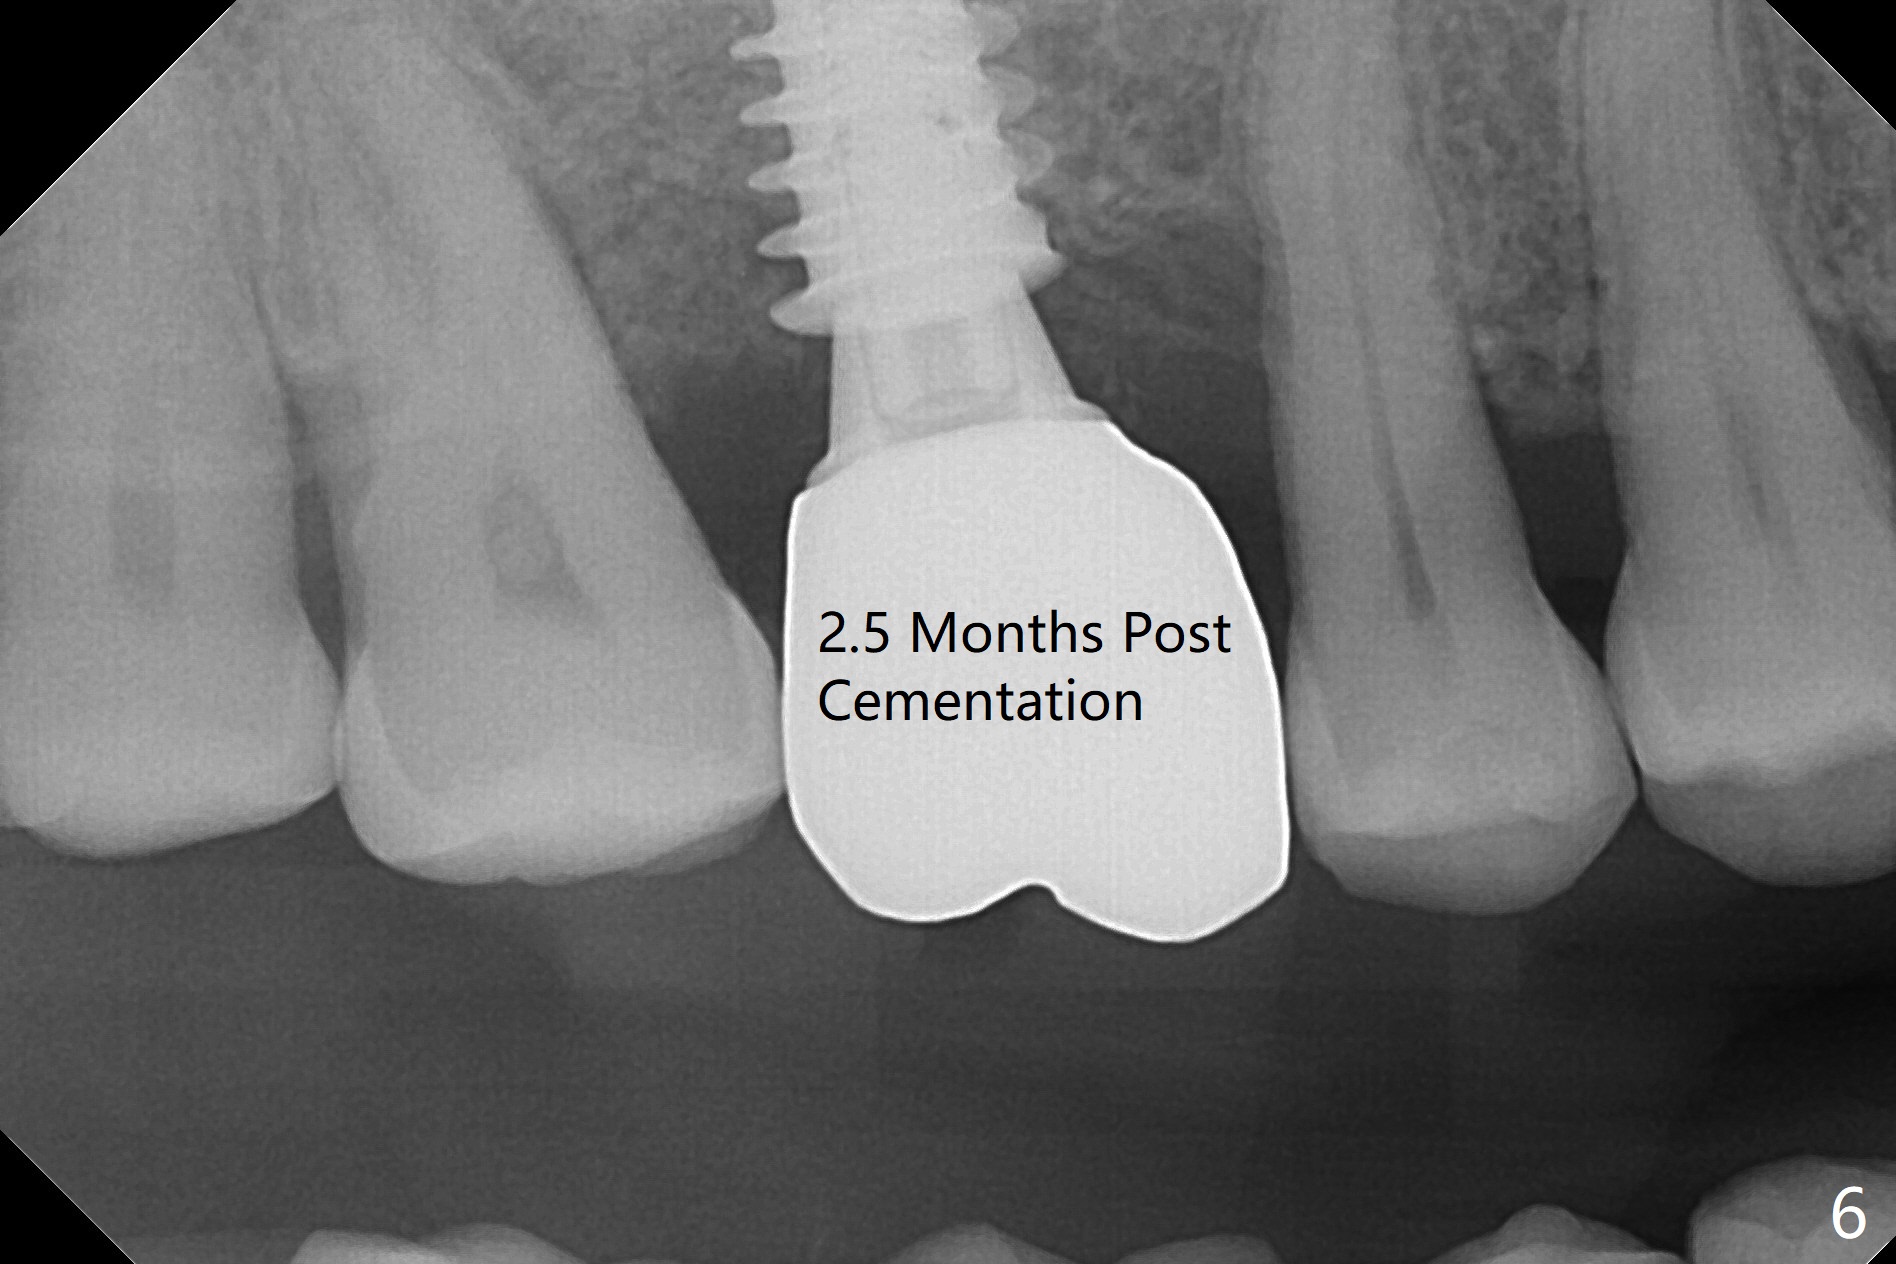

After extraction and debridement, osteotomy is initiated in the mesiobuccal socket free hand. Since the remaining bone is ~ 2 mm, the sinus floor is perforated suddenly. Fortunately the sinus membrane is not, as related to its thickening (similar to water ballooning, without symptom). Use 2-3.5 mm drills to enlarge the bony perforation (mainly lateral movement), followed by pushing bone graft upstairs with a curette (Fig.1 *); insert a 4x9 mm dummy implant (Fig.1) to determine the length of the final implant (Fig.2,3). A drawback of this case is the low torque (<20 Ncm), considering the thin bone. Following deeper implant placement, a 5.2x6(2) mm temporary abutment is placed for an immediate provisional to keep large amount of bone graft in place (Fig.3 *). There is no pain 1 week postop, while the immediate provisional remains stable partially because of the temporary abutment (Fig.4 ^). Four months postop, the temporary crown is loose. After removal of the temp and the temp abutment, gingival cuff is erythematous. A 6x4 mm healing abutment is placed. The bone graft (Fig.3 *) appears to have attached to the root of the neighboring tooth and the implant threads 7 months post op (COVID 19, Fig.5 arrowheads)). The bone graft appears to continue to merge with the neighboring root, bone and implant 10 months postop (2.5 months post cementation, Fig.6). The bone graft in the sinus seems to collapse and condense 10 months postop (Fig.7 *).